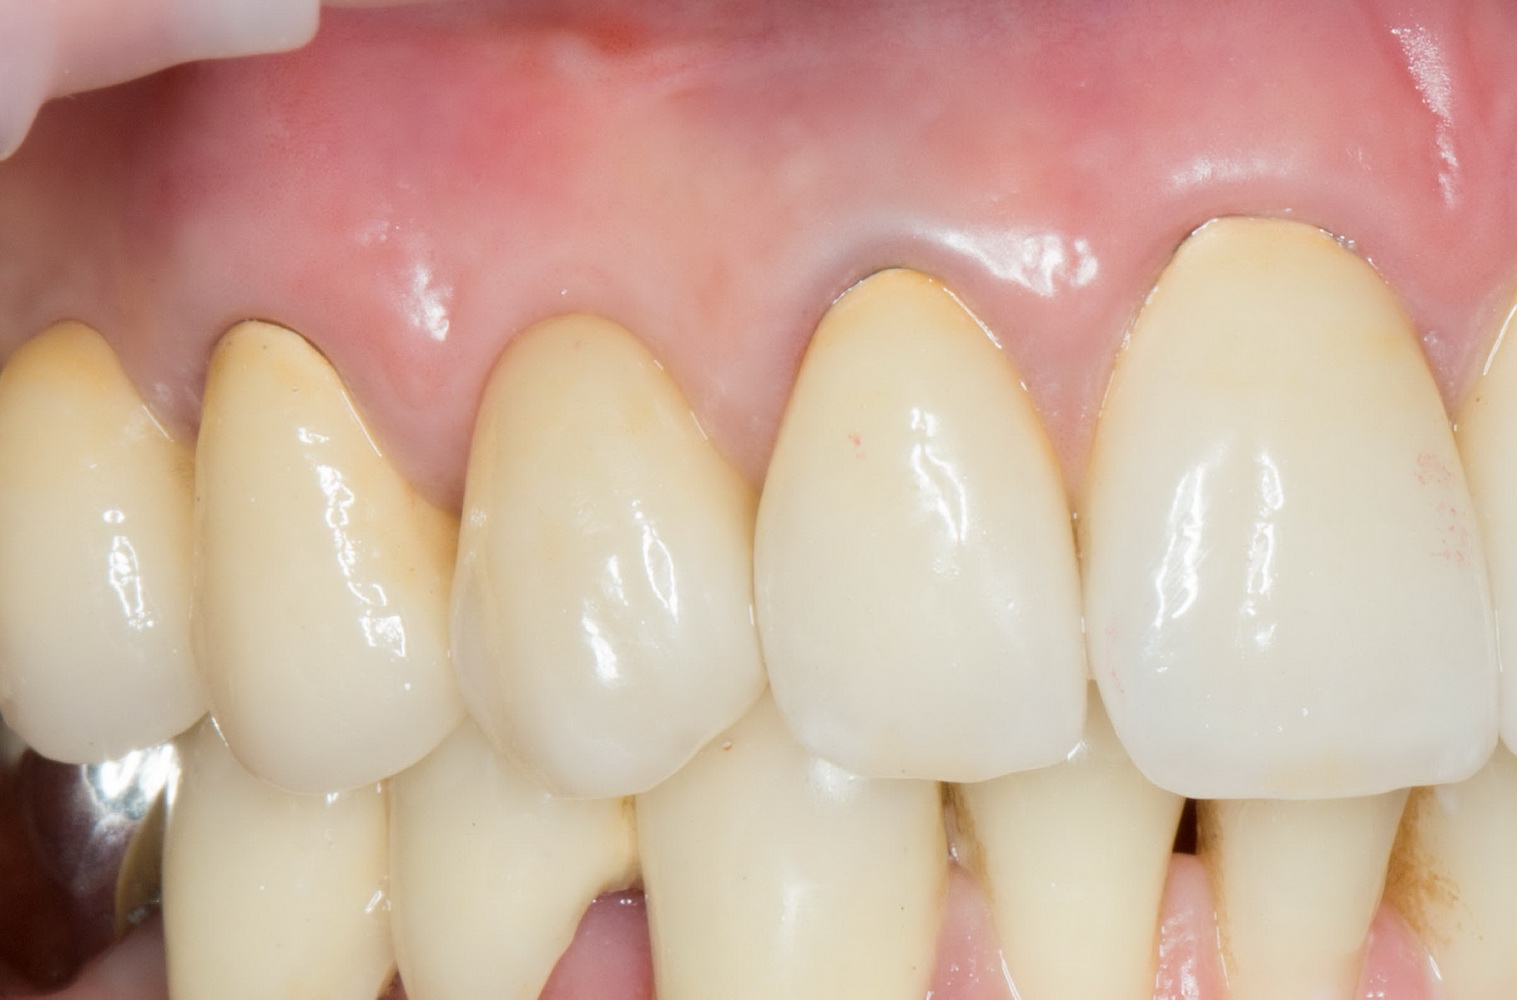

Итак, прошло, примерно, 6 месяцев после имплантации. На имплант клыка установлена постоянная металлокерамическая коронка. Вот она:

Или вот — так любят демонстрировать свои работы врачи-ортопеды:

Есть разница? Сейчас этот зуб выглядит лучше, чем окружающие.

По-моему, очень круто получилось. Давиду респект. Пациентке тоже.